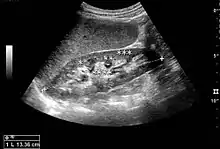

The kidney is divided into parenchyma and renal sinus. The renal sinus is hyperechoic and is composed of calyces, the renal pelvis, fat and the major intrarenal vessels. In the normal kidney, the urinary collecting system in the renal sinus is not visible, but it creates a heteroechoic appearance with the interposed fat and vessels. The parenchyma is more hypoechoic and homogenous and is divided into the outermost cortex and the innermost and slightly less echogenic medullary pyramids. Between the pyramids are the cortical infoldings, called columns of Bertin (Figure 1). In the pediatric patient, it is easier to differentiate the hypoechoic medullar pyramids from the more echogenic peripheral zone of the cortex in the parenchyma rim, as well as the columns of Bertin (Figure 2).[1]

Figure 1. Normal adult kidney. Measurement of kidney length on the US image is illustrated by ‘+’ and a dashed line. *Column of Bertin; ** pyramid; *** cortex; **** sinus.[1]

The length of the adult kidney is normally 10–12 cm, and the right kidney is often slightly longer than the left kidney. The adult kidney size is variable due to the correlation with body height and age; however, normograms for pediatric kidney size are available.[1]

Cortical thickness should be estimated from the base of the pyramid and is generally 7–10 mm. If the pyramids are difficult to differentiate, the parenchymal thickness can be measured instead and should be 15–20 mm (Figure 3). The echogenicity of the cortex decreases with age and is less echogenic than or equal to the liver and spleen at the same depth in individuals older than six months. In neonates and children up to six months of age, the cortex is more echogenic than the liver and spleen when compared at the same depth.[1]